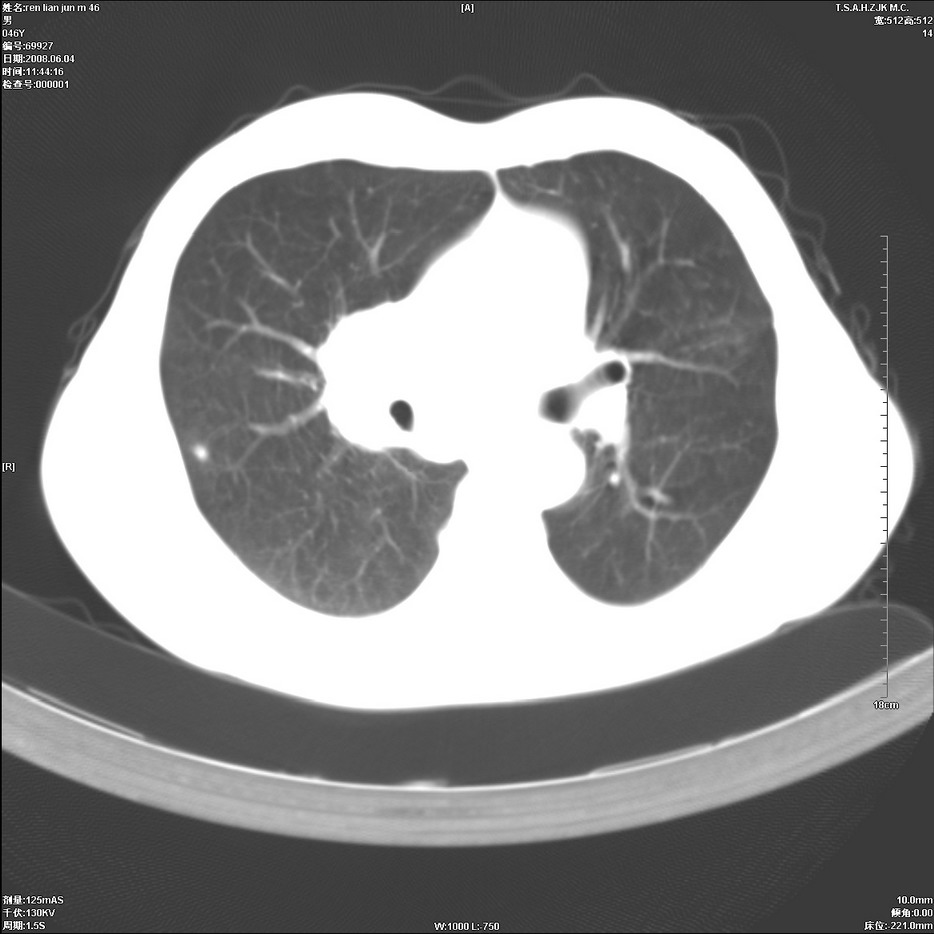

以下是引用qiu999在2008-6-5 17:14:00的发言:[br]考虑右肺中心型肺癌.颅内应做增强检查.

以下是引用形影不离在2008-6-5 19:18:00的发言:[br]右肺中心型肺癌并纵隔及左侧腋窝淋巴结转移,颅内应做增强检查。

以下是引用杀毒软件在2008-6-5 18:33:00的发言:[br]支持考虑右肺中心型肺癌,颅内病变是不是转移,不好说